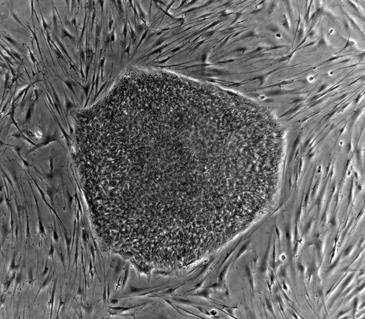

Investigadores del Centro Nacional de Investigaciones Cardiovasculares (CNIC), en España, han descubierto una proteína –Ezh1– que tiene un papel esencial para evitar que las células madre adultas proliferen hasta convertirse en oncogénicas, es decir, generar cáncer. El hallazgo se publica en la revista Cell Stem Cell.

La razón es que las células madre adultas tienen capacidad de autorrenovarse y seguir siendo células madre o continuar la vía de diferenciación para la que están programadas y, por lo tanto, inducir uno o más tejidos maduros, funcionales y plenamente diferenciados.

El hallazgo recién publicado en Cell Stem Cell identifica cómo la desaparición de un factor esencial para el mantenimiento de células madre embrionarias también juega un papel clave en el control homeostático de las células madre hematopoyéticas.